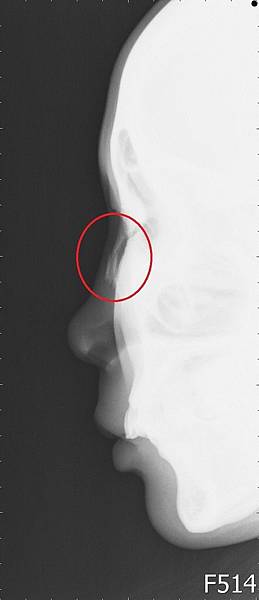

幫她照了鼻骨的X 光

從側面看非常清楚

一直線的鼻骨在一半的地方往下凹折

表示一個正面的力量擊向鼻子